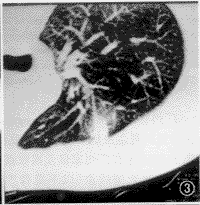

CT扫描,12例均有明显异常病灶显示。本组病例胸部CT表现包括:(1)小结节病灶 10例,结节影直径均在1 cm以下(范围0.5~1.0 cm),位居肺野外带胸膜下部(图1),其中8例小结节影周缘可见磨玻璃样密度的晕圈,即月晕征(图2,3)。(2)小斑片局灶性磨玻璃样密度影,在肺野外带浸润(图4),斑片与正常肺临界缘呈“小三角形”改变7例,部分在肺尖部散在,形似浸润型结核(图5)。(3)外带支气管血管束呈局灶性“Y”形增粗3例(图6)。上述小结节影、小斑片淡薄影均在两肺周边区域呈多灶性散在分布,没有大叶融合倾向。全组病例纵隔、肺门部未见肿大淋巴结。

图3 左上肺后段外带“结节月晕征”